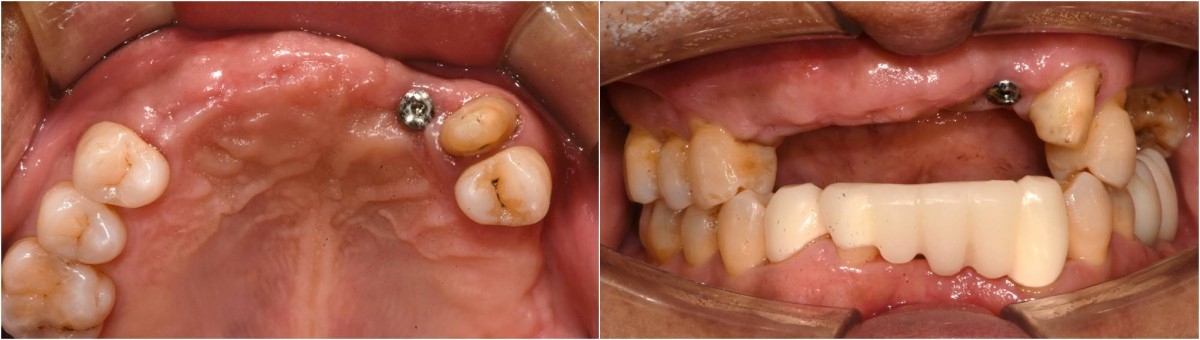

In the anterior maxilla, implant-supported fixed partial denture.

<GCpbc> A 58-year-old male is a patient undergoing implant installation in various parts. The old Br of the anterior maxilla has fallen

off and it is no longer possible to maintain it even temporarily, so a

treatment plan for the anterior teeth was made.